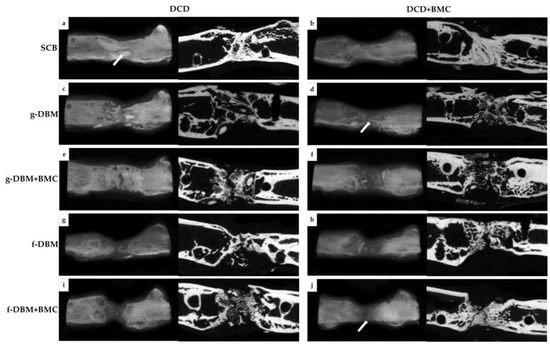

2.5. µCT (Microcomputertomographie)

3.3. Bone Formation—Bone Score and Bone Mineral Density